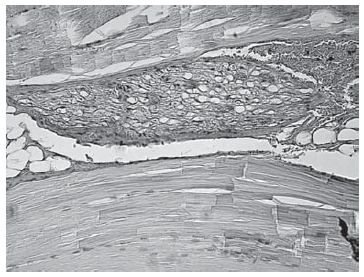

При гистологическом исследовании материала (спинномозговых нервов и их чувствительных узлов крыс), изъятого на 30-е сутки, изменений в нервной ткани не выявлено, что может свидетельствовать о полном ее восстановлении после воздействия радиочастотной импульсной модуляции (рис. 4).

Рис. 4. Чувствительный узел спинномозгового нерва спустя 30 суток после воздействия. Окр. гематоксилин + эозин, ув.×200

Данные нашего эксперимента на животных подтверждают ранее опубликованные результаты W. Hamann et al. [11], которые изучали изменения в спинномозговых нервах и их чувствительных узлах у лабораторных животных спустя 14 суток после проведения импульсной радиочастотной модуляции и пришли к выводу, что процедура не вызывает значительных гистологических изменений. Кроме того, в исследовании S. Erdine et al. [9] на лабораторных крысах было проведено сравнение гистологических изменений в чувствительных узлах спинномозговых нервов после воздействия непосредственно радиочастотной энергией при температуре 67°С в первой группе и импульсной радиочастотной модуляцией во второй. В результате в первой группе были выявлены дегенеративные процессы в митохондриях с признаками нарушения энергетического обмена, однако во второй группе никаких изменений выявлено не было.